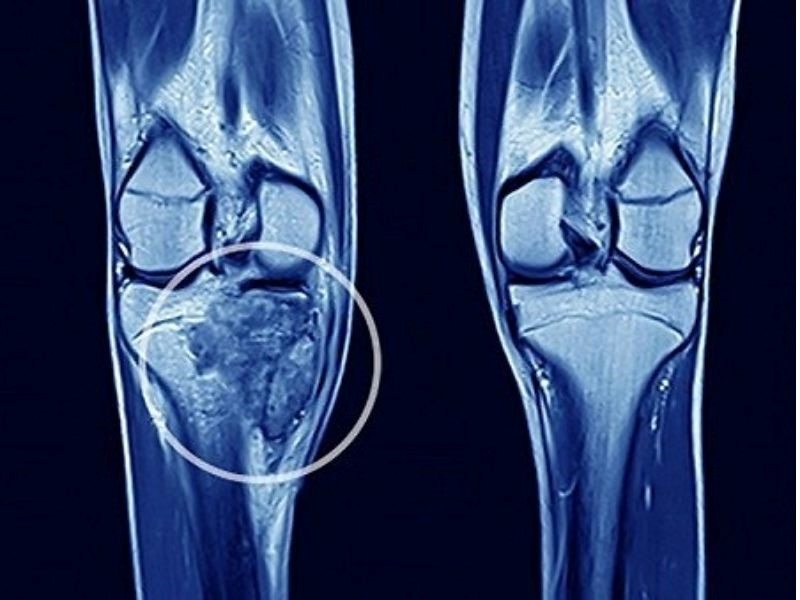

Căn bệnh ung thư xương rất nguy hiểm

Ung thư xương là một dạng bệnh lý hiếm gặp nhưng vô cùng nguy hiểm, diễn ra khi các tế bào trong xương, sụn hoặc mô liên kết tăng trưởng một cách bất thường và không được kiểm soát. Dù không phổ biến như nhiều loại ung thư khác, nhưng tỷ lệ di căn của ung thư xương lại rất cao. Bệnh được chia thành hai loại chính: ung thư xương nguyên phát và ung thư xương thứ phát.

Ung thư xương nguyên phát phát sinh trực tiếp từ xương và có nhiều loại khác nhau. Một số dạng phổ biến bao gồm sarcoma xương, thường xuất hiện ở xương tay, chân và xương chậu; sarcoma Ewing, thường xảy ra ở xương chậu, xương sườn và mô mềm; sarcoma sụn, thường gặp ở người cao tuổi; và u tế bào khổng lồ của xương, có thể lành tính hoặc ác tính và thường gặp ở người trẻ.